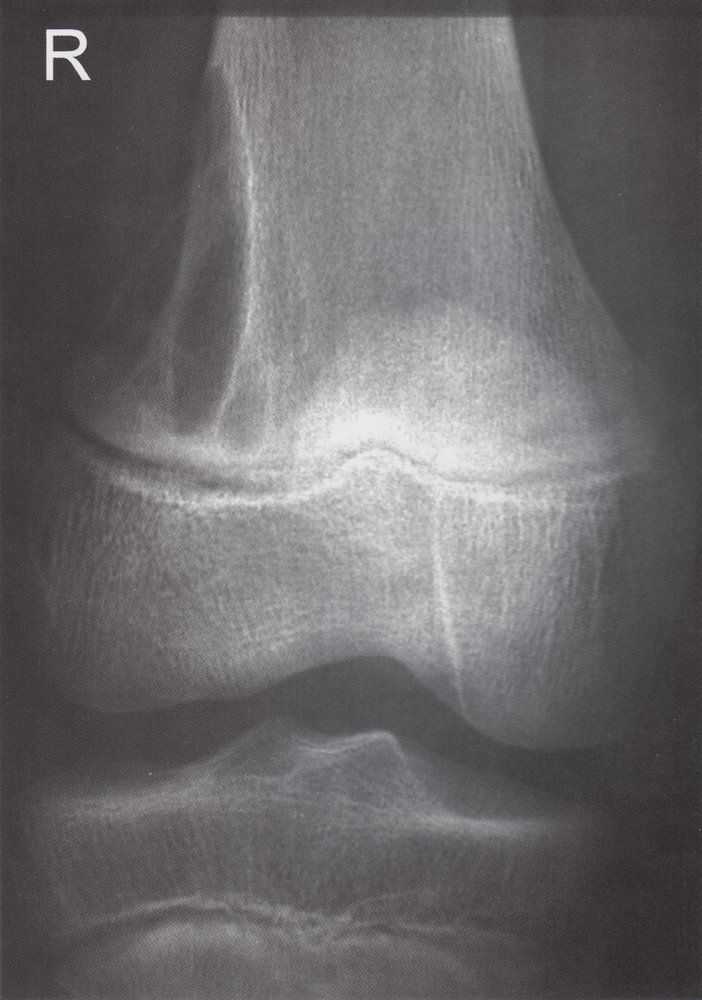

Giant-cell tumor (osteoclastoma)

• Tumor arising from giant cells of the bone marrow

• Peak incidence: 20–40 years

• Epiphysis of long bones (usually around the knee)

• Local pain and swelling

• Pathological fractures

• X-ray: multicystic osteolytic lesions (soap-bubble appearance)

• Description: benign but locally aggressive tumor composed of giant cells that arise from the bone marrow [1]

• Epidemiology: peak incidence between 20 and 40 years

• Clinical features

• Found in the epiphysis or metaphysis of long bones (especially knee region)

• Limited range of motion

• Diagnostics